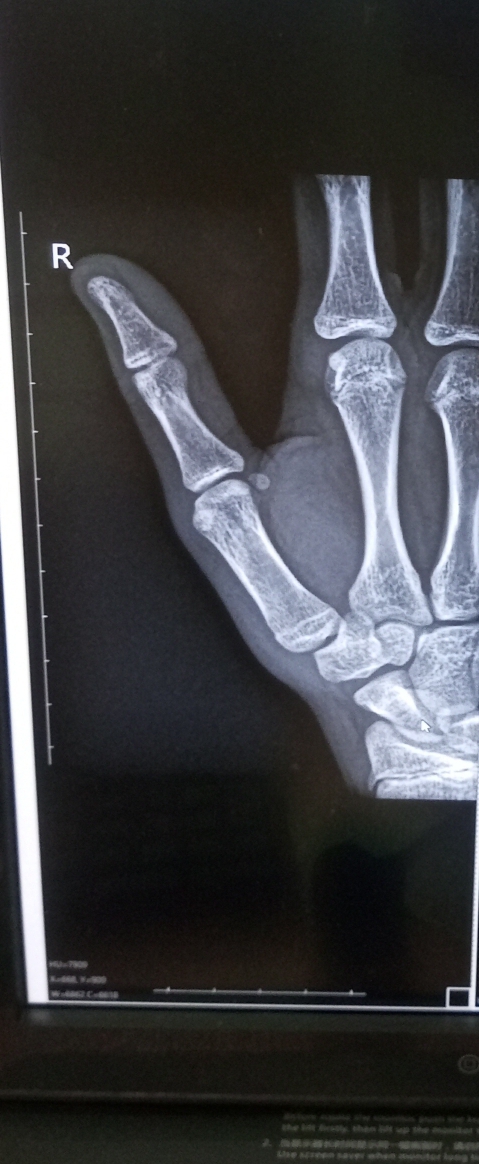

Все ли нормально с большим пальцем на руке?   1 ответ

Полгода назад был сломан большой палец. В среду после небольшого удара он сильно опух и появился большой синяк, при движении сильно болит. Снимки свежие.